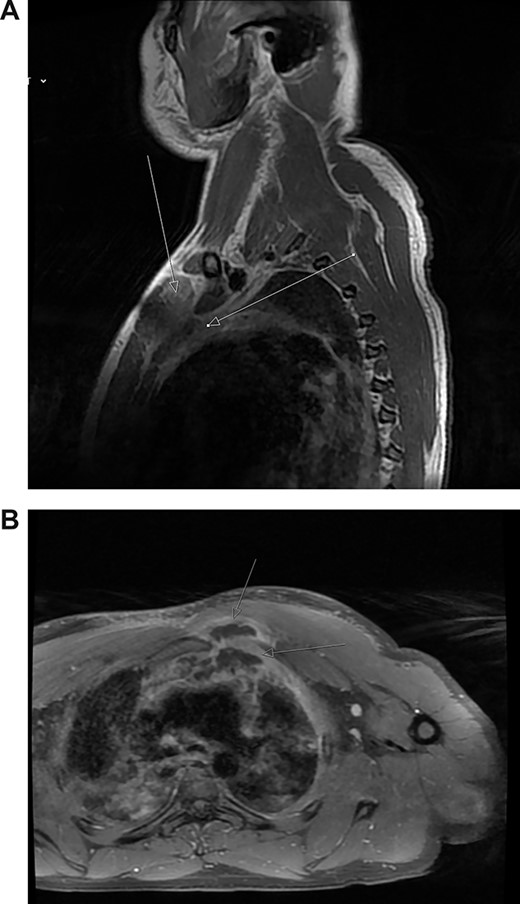

Magnetic resonance imaging (MRI) performed 1 day after admission showed inflammation and oedema at the superior and medial aspect of the left pectoralis muscle suggesting myositis. This inflammation extended to the left second sternocostal joint, the superior and posterior border of the manubrium abutting the anterior margin of the left brachiocephalic vein to indicate mediastinitis (Fig. 2a). No abnormality was seen in the joints, bone or bone marrow.

(A) Post-contrast MRI scan showing areas enhancement around pectoralis major (myositis) with extension into the mediastinum (mediastinitis) (white arrows). (B) New rim-enhancing collections within left pectoralis major muscle. The collection appears to extend posteriorly into the anterosuperior mediastinum (white arrows)

The patient was commenced on a regimen of intravenous flucloxacillin and clindamycin. Blood cultures subsequently grew methicillin-sensitive S. aureus. Despite antibiotics, his symptoms worsened. His neutrophils and CRP increased to 16 000 cells/μL and 404 mg/L, respectively. Repeat MRI scan on day 5 showed further progression of myositis with new rim-enhancing collections within the left supero-medial pectoralis major muscle extending inferiorly and posteriorly to the first rib sternal articulation. The collection also extended through the left first rib sternal articulation into the anterosuperior mediastinum (Fig. 2b). Furthermore, there was now compression of the left brachiocephalic vein.